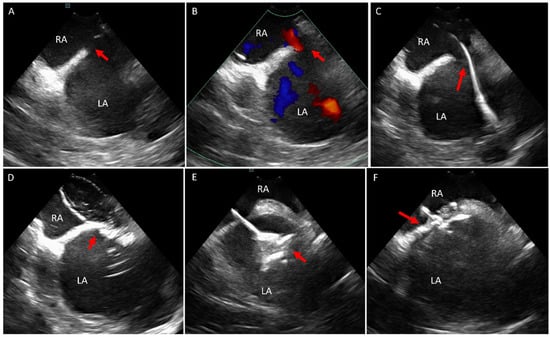

6.1. Baffle Leak Occlusion